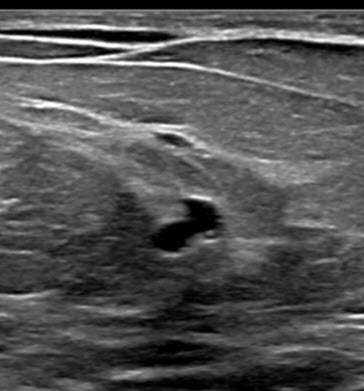

Ultrasound:

Radial sclerosing lesions have a variable appearance on ultrasound imaging and are frequently not visualized. They are typically found on targeted ultrasound examination for a mammographically detected lesion. When they are seen, they may present as an irregular hypoechoic mass or parenchymal distortion with ill-defined borders +/-posterior acoustic shadowing (Fig 1b). They may also present as a round or oval mass (Fig 2b) or a focal area of shadowing without a discrete mass. Findings that do not confirm but may favor a RSL over carcinoma include the absence of an echogenic halo, shadowing, or breast architectural distortion and/or the presence of tiny cystic changes(2,3).